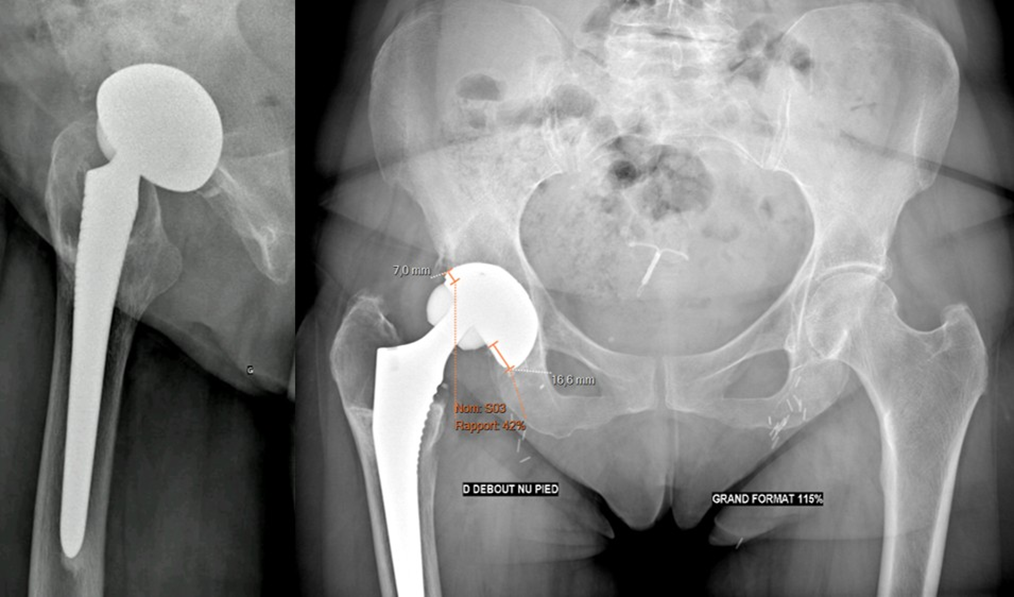

of the femoral head compared to the 2013 postoperative images (Figure 2). Wear measurements were obtained by adapting the method of Charnley et al. [4] used for polyethylene bearings, as no validated score exists for ceramic wear measurement on radiographs. CT confirmed cranial migration of the femoral head without clear fracture of the ceramic liner or head, and revealed femoral and acetabular periprosthetic granuloma (Figure 3).

Figure 2 : Anteroposterior pelvic and lateral right hip radiographs, 2024, showing 42?centricity of the prosthetic femoral head.

Figure 3: Coronal CT scan of the right hip, 2024.

Given the disabling pain and probable implant wear, a one-stage acetabular component and femoral head revision was indicated and performed in July 2024.